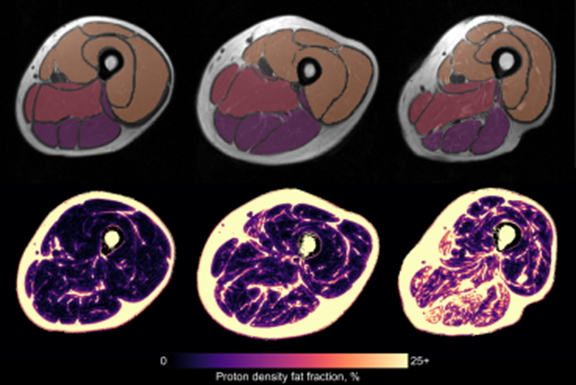

- Quantitative Susceptibility Mapping (QSM): This measures the magnetic susceptibility related to iron and myelin content in tissues. In chronic MS lesions, increased susceptibility is observed, potentially reflecting iron deposition, and in NAWM susceptibility changes indicate demyelination and potential iron accumulation.

- Myelin water imaging: This approach separates the signal from water trapped between myelin bilayers (termed myelin water) and water in other physical spaces and yields a validated biomarker of myelin content called myelin water fraction (MWF). In MS lesions, MWF is heterogeneously reduced, reflecting varying degrees of demyelination, Laule said.